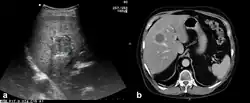

Die Larve durchdringt das Epithelgewebe der Darmwand und gelangt über die Mesenterialvenen und die Pfortader zur Leber des Zwischenwirts, sie kann aber in Ausnahmefällen auch Lunge, Herz oder Milz befallen. Innerhalb des Gewebes setzt sich die Onkosphäre fest und bildet als zweites Larvenstadium die Metazestode oder Finne, die auch als Echinococcus alveolaris[21] bezeichnet wird. Sie ist eine mit gallertartiger Masse gefüllte Blase, die gegen das sie umgebende Organ durch eine Wand aus Bindegewebe abgegrenzt ist. Wie dieser Vorgang ausgelöst und gesteuert wird, ist nicht bekannt.

Aus der Wand der Metazestode entspringen im weiteren Verlauf der Infektion durch Knospung stetig weitere Finnen; es entsteht eine Larvenstruktur, die aus einer Anhäufung blasenartig erscheinender Finnen besteht und das Wirtsgewebe infiltriert. Sie wird daher als Hydatide des alveolären (blasenartigen) Typs von der Hydatide des zystischen Typs des Hundebandwurms abgegrenzt, bei dem durch eine Knospung nach innen eine große Hydatidenblase gebildet wird. Im Rahmen der Knospung können sich Zellverbände oder einzelne Zellen der Metazestode ablösen, über die Blutbahn des Wirts andere Organe erreichen, sich dort festsetzen und weitere Befallsherde bilden.

Beim Menschen als Fehlwirt ist die Knospung der Metazestoden stark verlangsamt und es bilden sich allenfalls wenige Protoscolices. Die Metazestode wächst nach außen, und es kommt in ihrem Zentrum zu Abbauprozessen. So entsteht eine langsam zunehmende Masse aus nekrotisiertem Gewebe, das von einer relativ dünnen Schicht lebenden Parasitengewebes umhüllt ist.

Zur Identifizierung der Larven in Zwischenwirten wird die makroskopische oder mikroskopische Untersuchung oder eine DNA-Analyse herangezogen. Beim Menschen werden zur Diagnose verschiedene serologische Untersuchungen angewendet, die eine Infektion erkennen lassen, bevor Symptome auftreten.